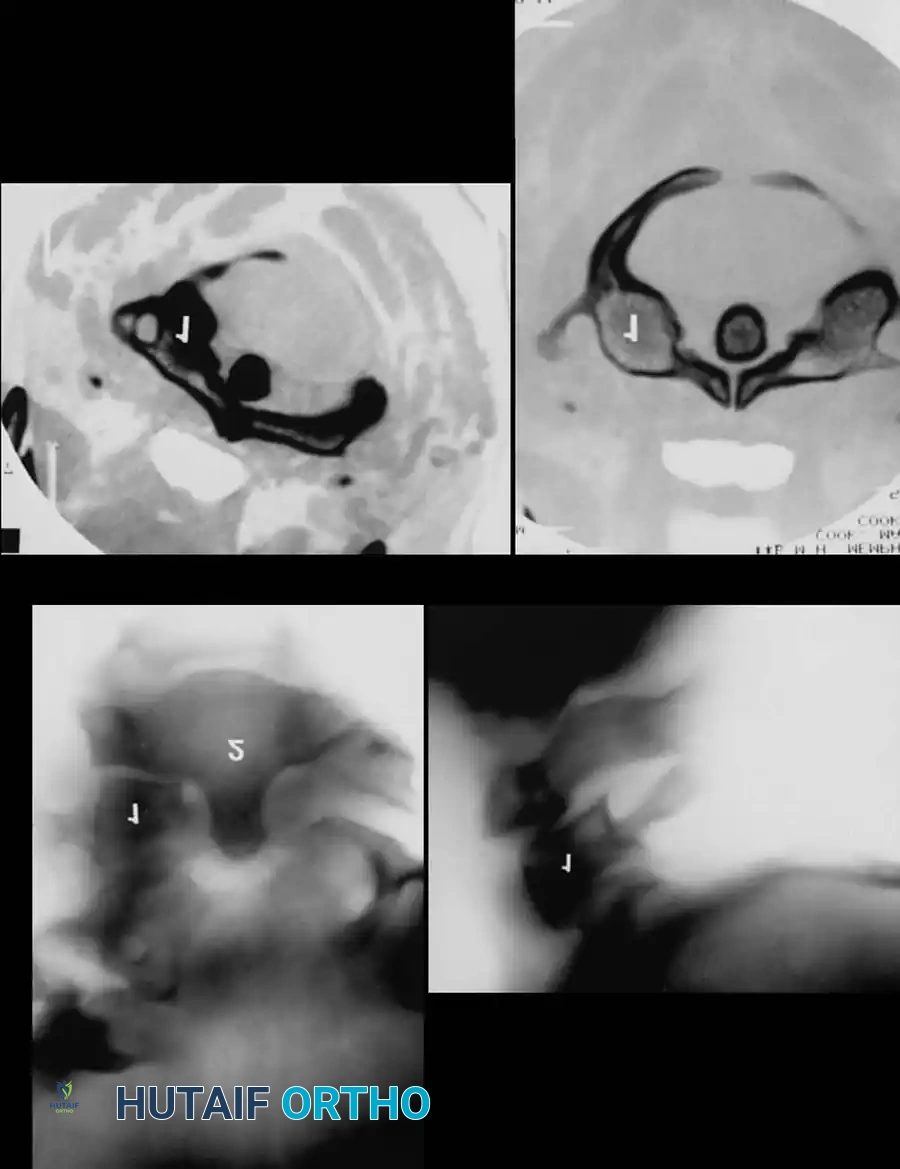

Diagnostic Modalities and The Stretch Test

While modern trauma protocols rely heavily on high-resolution CT and MRI, the Stretch Test remains a classical biomechanical tool for determining clinical instability in the lower cervical spine when advanced imaging is unavailable or equivocal.

Surgical Warning: The stretch test is strictly contraindicated in an obviously unstable injury. It must always be performed under the direct, continuous supervision of the attending orthopedic or neurosurgical consultant.

🔪 Surgical Technique 35-1: The Stretch Test Protocol

- Preparation: Apply traction through secured cranial skeletal traction (Gardner-Wells tongs). A head halter is inadequate for the weights required and risks skin necrosis. Place a rolled towel under the patient’s neck to maintain a neutral lordotic contour.

- Baseline Imaging: Place the radiographic film/detector as close to the neck as possible. Position the X-ray tube 72 inches away to minimize magnification, and obtain a baseline lateral radiograph.

- Incremental Loading: Begin with 10 lb of traction. Increase the weight in 5-lb increments.

- Monitoring: After each 5-lb addition, perform a strict neurological examination and obtain a repeat lateral radiograph.

- Viscoelastic Creep: Allow at least 5 minutes between incremental weight applications to account for the viscoelastic creep of the disrupted ligamentous structures.

- Endpoints: Continue until one of the following endpoints is reached:

- One-third of the patient's body weight is applied.

- A maximum of 65 lb is reached.

- Positive Test (STOP IMMEDIATELY): Any neurological deterioration occurs, interspace separation exceeds 1.7 mm, or the angular difference between the prestretched and loaded condition exceeds 7.5 degrees.